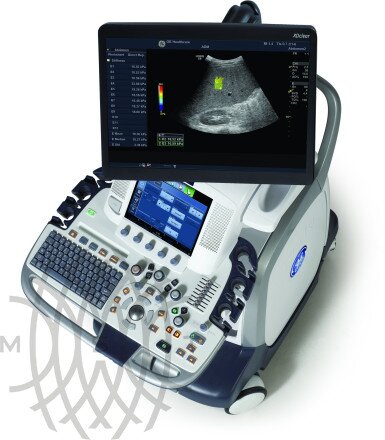

GE Logiq E9 XDclear аппарат УЗИ

Характеристики GE Logiq E9 XDclear аппарат УЗИ

- Страна производства: США

- Тип устройства: Стационарный

- Класс аппарата: Экспертный

- 22" жидкокристаллический монитор высокого разрешения на свободно регулируемом кронштейне.

- Эргономичный интерфейс пользователя с 10,4" цветной сенсорной панелью.

- 4 функционирующих бесштырьковых разъема для датчиков.

- Встроенный жесткий диск 500 Гбайт.

- DVD-привод для записи компакт-дисков.

LOGIQ E9 XDclear 2.0 — это непревзойденные возможности диагностики при проведении ультразвуковых исследований у пациентов любой комплекции и возраста. Система позволит получить достоверные результаты как при сканировании технически сложных пациентов с избыточным весом, так и для новорожденных с небольшой массой тела.

В новой версии системы были модернизированы практически все элементы, отвечающие за процесс формирования изображений — от сигнальных последовательностей датчиков до алгоритма повышения четкости на уровне отдельных пикселей, в результате платформа XDclear 2.0 позволяет получить более высокое разрешение одновременно с увеличенной глубиной проникновения.

LOGIQ E9 XDclear 2.0 — это непревзойденные возможности диагностики при проведении ультразвуковых исследований у пациентов любой комплекции и возраста. Система позволит получить достоверные результаты и при сканировании технически сложных пациентов с избыточным весом, и для новорожденных с небольшой массой тела.

В новой версии системы были модернизированы практически все элементы, отвечающие за процесс формирования изображений — от сигнальных последовательностей датчиков до алгоритма повышения четкости на уровне отдельных пикселей, в результате платформа XDclear 2.0 позволяет получить более высокое разрешение одновременно с увеличенной глубиной проникновения.

Благодаря усовершенствованной акустической архитектуре, более мощной подсистеме постобработки и высоконтрастному OLED-монитору удалось значительно улучшить рабочие характеристики устройства по сравнению с предыдущей версией.

- Существенное повышение контрастности более чем на 20% даёт возможность различать даже самые небольшие детали на изображении.

- Вдвое увеличенное пространственное разрешение позволяет производить идеальную фокусировку.

- Больший охват — на 170% больше полезной информации на экране.

Также стоит отметить высокую мобильность системы, которая позволяет легко перемещать её в пределах медицинского учреждения, ведь новый Logiq E9 на 20% меньше предшественника и на 45 кг легче него.